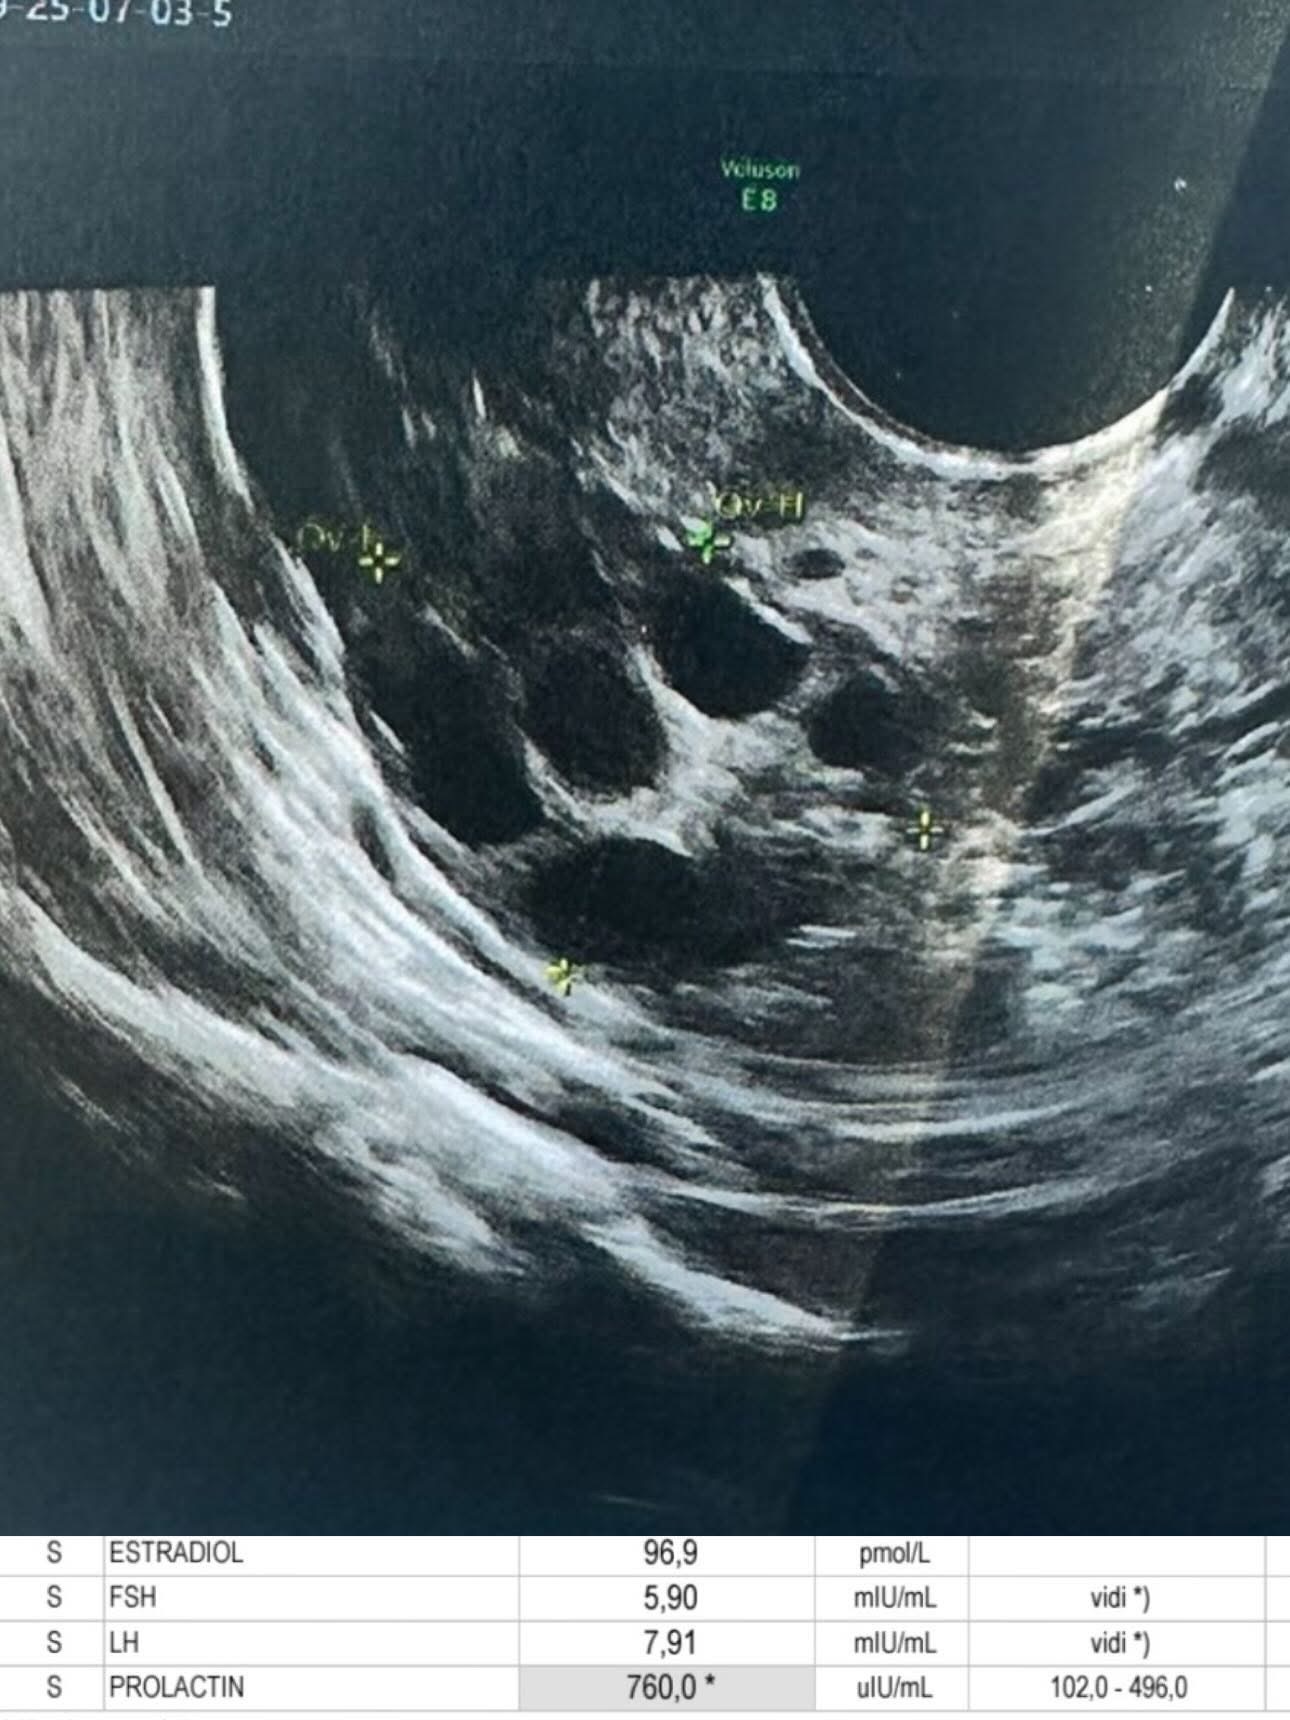

Tokom proteklih nekoliko godina, Aleksandra se suočila s raznim zdravstvenim problemima koji su značajno uticali na njen život i karijeru. Kako je sama istaknula, borila se sa teškim kožnim promjenama uzrokovanim terapijom, hormonskim disbalansom i cistama na jajnicima. Ovi fizički problemi nisu se samo odrazili na njeno zdravlje, već su dodatno pogoršali njeno mentalno stanje, čineći svakodnevni život izuzetno izazovnim. Često su se javljali i simptomi anksioznosti, što je dodatno otežavalo njen proces oporavka.